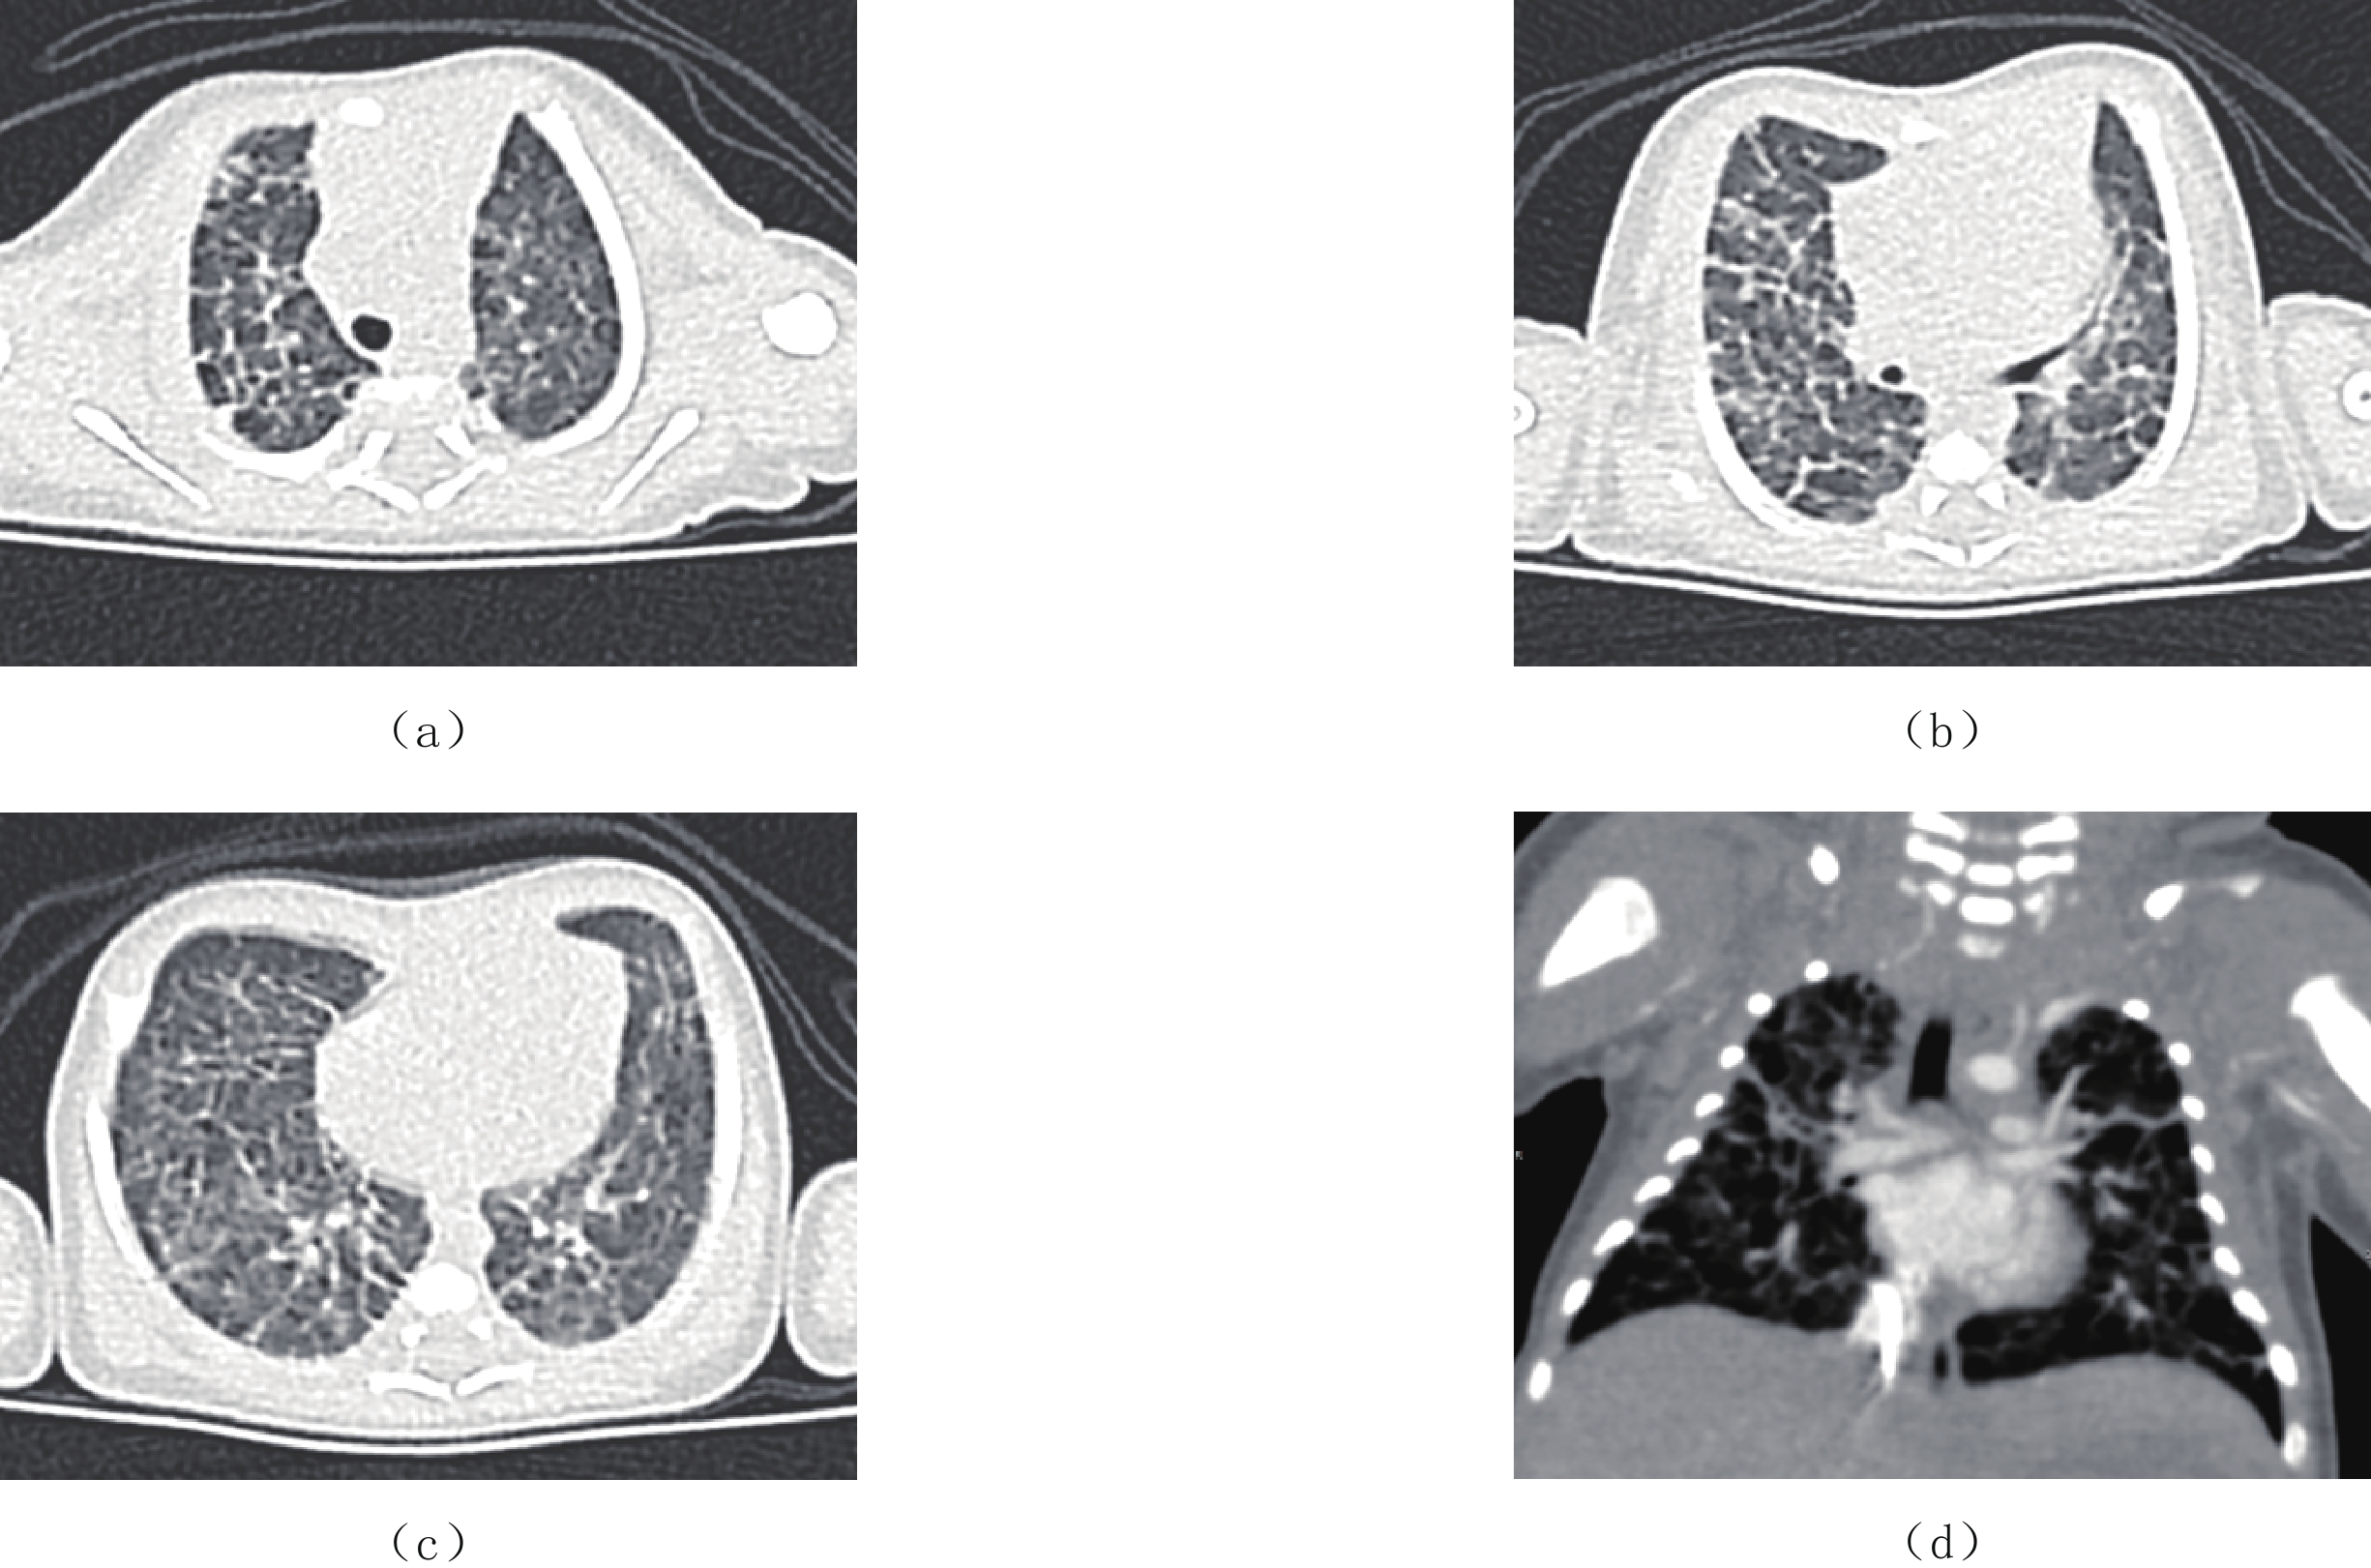

X线胸部平片表现为弥漫的肺间质病变和或囊性变,高分辨CT扫描为最佳检查方法,表现为弥漫性或节段性的一侧或双侧肺小叶间隔增厚,伴磨玻璃影,可有少量的胸腔积液,纵隔增宽不显著及肺门增大不明显,弥漫性受累多见于新生儿及婴幼儿(图4)。

肺淋巴管扩张症需与弥漫性肺淋巴管瘤病(diffused pulmonary lymphangiomatasis,DPL)相鉴别,后者很少在出生后新生儿期发病,病理上与肺淋巴管扩张不同的是,其淋巴管数量增多,形态异常,异常淋巴管间存在多发紊乱的复杂沟通,而原发性肺淋巴管扩张症中的淋巴管数量正常,大小和形状相对规则[10]。两种病变可通过肺活检证实。

弥漫性肺淋巴管瘤为肺内淋巴回流异常,淋巴液瘀滞在肺间质、纵隔及支气管周围的淋巴管内,CT表现为肺内弥漫性的小叶间隔增厚呈粗大网格状改变,纵隔明显增宽,大血管周围为弥漫的低密度灶,肺门影增大,甚至增宽的纵隔影将肺门掩盖,常可见胸腔积液。